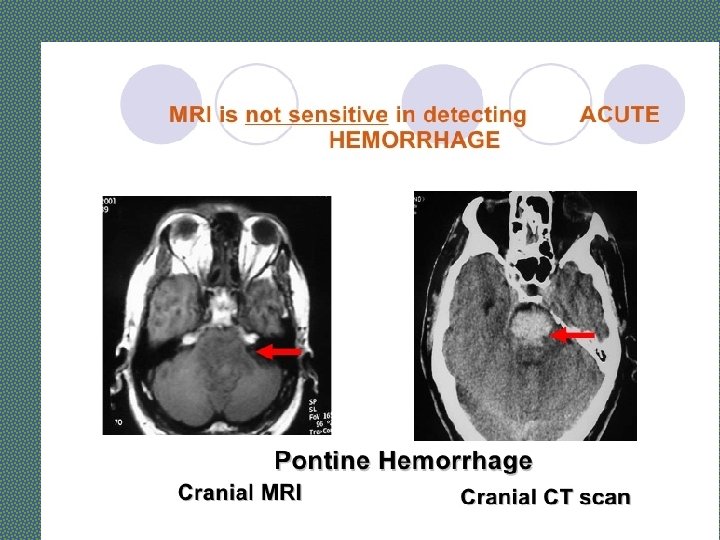

Investigations of Stroke Ø Brain Computed Tomography (CT) Scan Ø Magnetic resonance imaging (MRI) Ø Computed Tomography Arteriogram and Magnetic Resonance Arteriogram: Aneurysm, AV malformation Ø Carotid Ultrasound Ø ECG and Echocardiography Ø Lumber Puncture: Subarachnoid Hemorrhage

Investigations - STROKE • Imaging in Acute Stroke. • Non-contrast CT: will demonstrate haemorrhage immediately but cerebral infarction is often not detected or only subtle changes are seen initially.